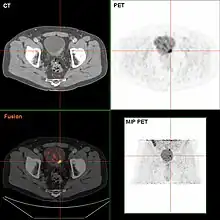

If invasive or high grade (includes carcinoma in situ) cancer is detected on TURBT, an MRI and/or CT scan of the abdomen and pelvis or urogram and CT chest should be conducted for disease staging and to look for cancer spread (metastasis).[56] Increase in alkaline phosphatase levels without evidence of liver disease should be evaluated for bone metastasis by a bone scan.[57] Although 18F-fluorodeoxyglucose (FDG)-positron emission tomography (PET)/CT has been explored as a viable method for staging, there is no consensus to support its role in routine clinical evaluations.[54]